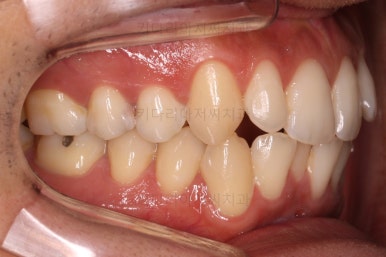

초진 시 입안의 모습입니다.

앞니가 약간 삐뚠 것 말고는 큰 문제는 없어보이네요.